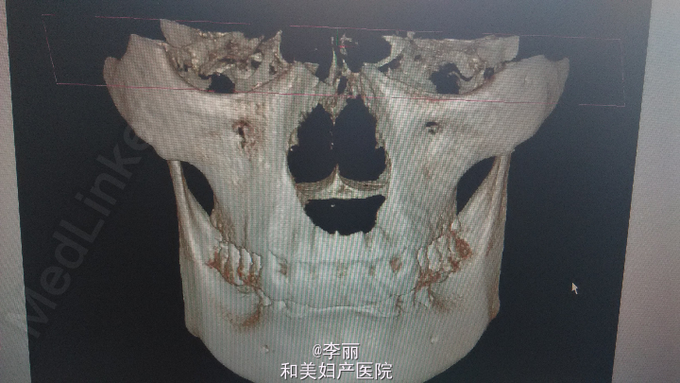

上颚部前正中可见一肿物,梭形,2*4CM,前界至11,21舌侧,后界至硬腭中份,11,21叩诊不适,我院CT显示上颚前部见一囊性低密度影像病变,约36*3*27CM,边界清楚边缘整齐,鼻底及腭侧骨板完全吸收,结果考虑鼻腭囊肿可能性大

上颌骨囊肿,鼻腭囊肿?全麻下行上颚部肿物切除术,根尖切除术,牙槽骨修整术

可与根尖囊肿鉴别,主要靠病理结果支持诊断